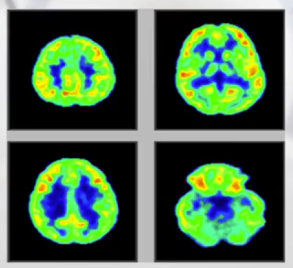

(5)PAT正电子成像: 上述为解剖结构成像,随着成像计算的发展,出现了功能和代谢成像的图片,如PAT正电子成像——对人体内,尤其是氧的消耗量的大小来分析不同组织结构的特征,不仅可以看到解剖结构,更多的是描绘人的新陈代谢或者人体功能的描述。因此这种成像对癌症,比如一些病变的早期形成过程有很好的描述,帮助医生早诊断、早治疗